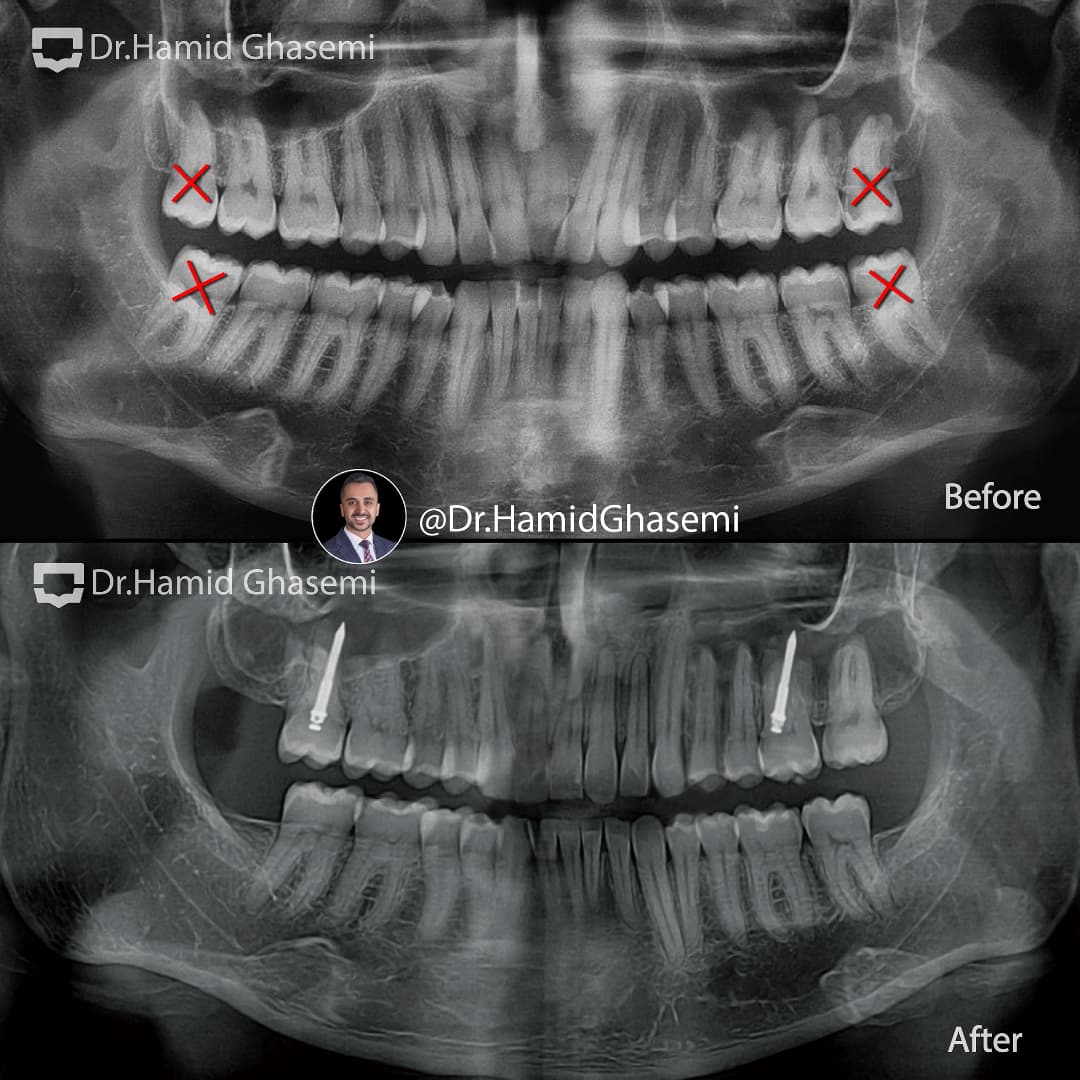

کشیدن دندانهای عقل

دیستالیزیشن قوس فکی با استفاده از TADs system

3rd molars extraction

Distalization of both arches using TADs system